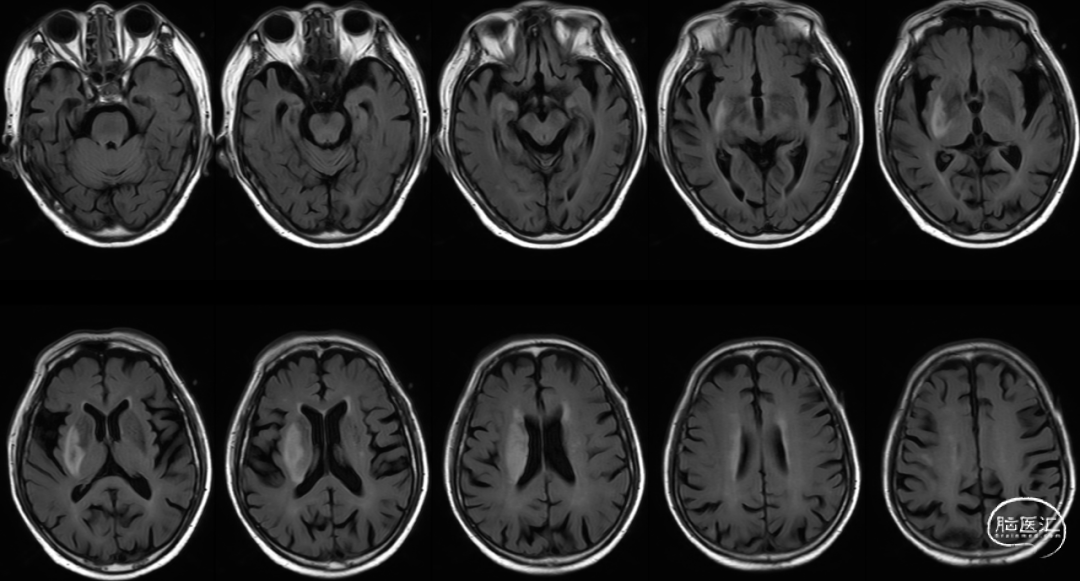

Cranial Cervical & Aortic arch MRA。

RICA C1闭塞,来自RACA丰富的软膜支代偿。

Reexamination Cranial MRA。